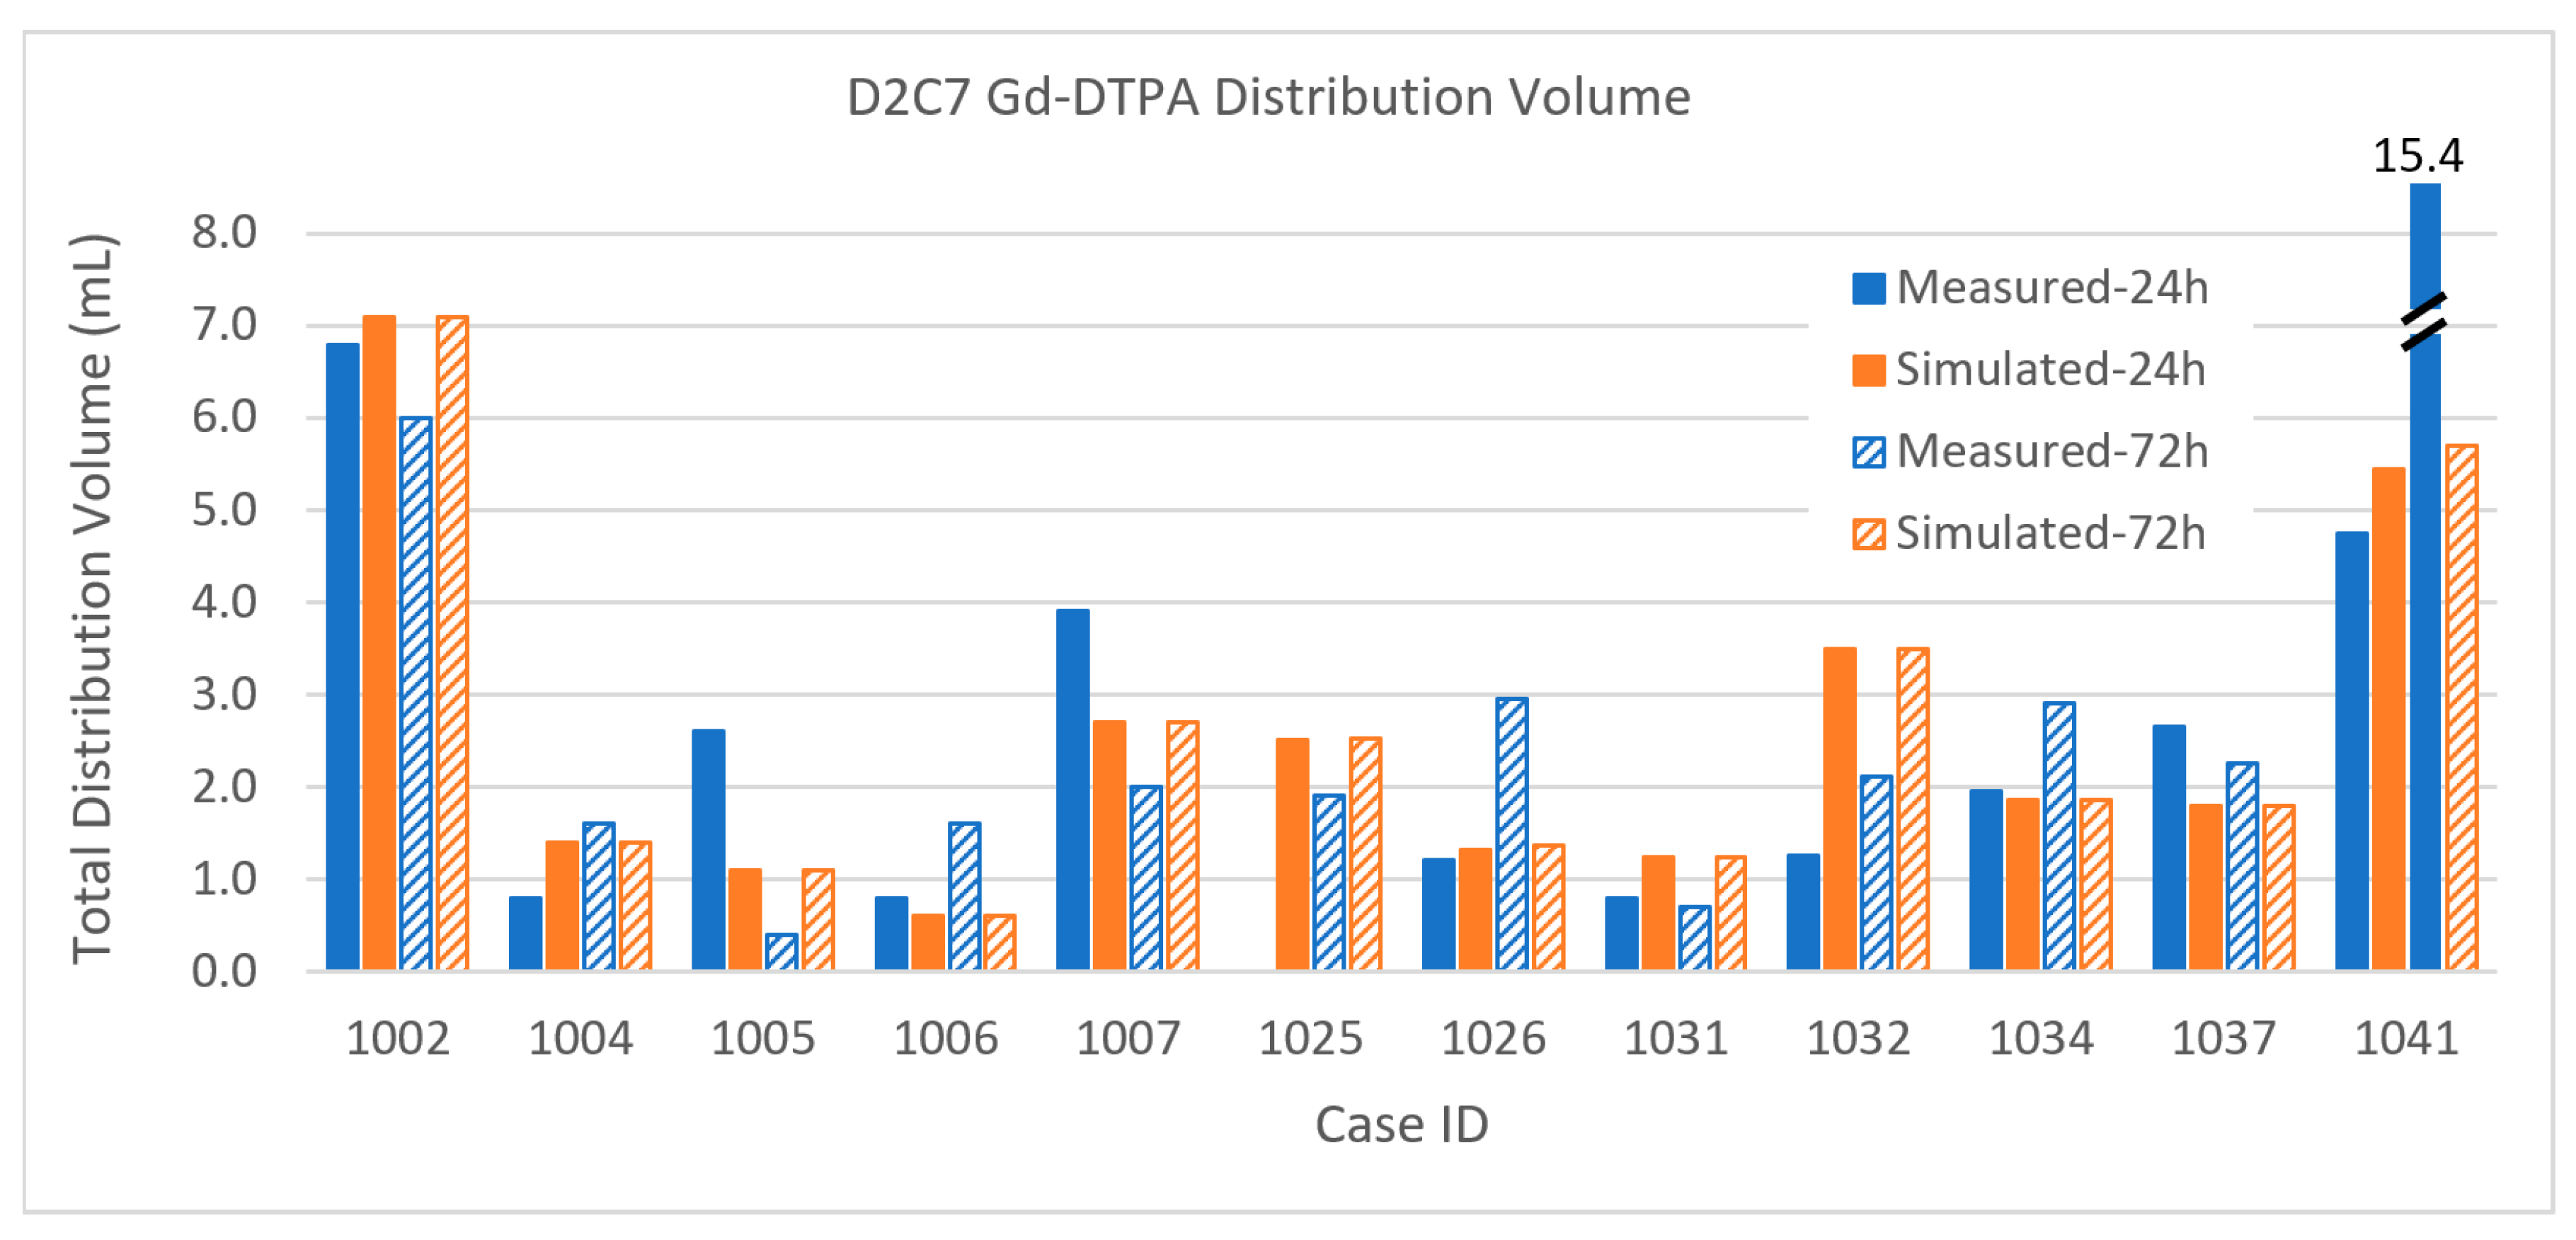

3.2.1. Total Distribution Volume

3.2.3. Error Measure

Appendix A. Table of Data for All Infusions

| CaseID | Distribution Volume (mL) | Coverage (%) | Tumor Volume (mL) | |||||||||||

|---|---|---|---|---|---|---|---|---|---|---|---|---|---|---|

| [n catheters] | Enhancing Tumor | Margin | Total | Enhancing Tumor | Margin | Enhancing | Margin | |||||||

| 24 h | 72 h | 24 h | 72 h | 24 h | 72 h | 24 h | 72 h | 24 h | 72 h | |||||

| D2C7 P1001 | Gad | Measured | 1.0 | 0.6 | 1.9 | 0.0 | 3.3% | 0.0% | 0.6% | 0.0% | 30.1 | 95.0 | ||

| D2C7 P1002 | Gad | Measured | 1.5 | 2.0 | 5.3 | 4.0 | 6.8 | 6.0 | 15.0% | 20.0% | 6.2% | 4.7% | 10.0 | 86.0 |

| D2C7 P1004 | Gad | Measured | 0.8 | 1.5 | 0.1 | 0.1 | 0.8 | 1.6 | 9.9% | 19.0% | 0.1% | 0.1% | 7.9 | 81.0 |

| D2C7 P1005 | Gad | Measured | 0.7 | 0.1 | 1.5 | 0.2 | 2.6 | 0.4 | 10.0% | 1.5% | 1.6% | 0.2% | 6.6 | 96.0 |

| D2C7 P1006 | Gad | Measured | 0.6 | 1.2 | 0.2 | 0.4 | 0.8 | 1.6 | 7.2% | 14.5% | 0.2% | 0.4% | 8.3 | 94.3 |

| D2C7 P1007 | Gad | Measured | 1.0 | 0.2 | 2.9 | 1.8 | 3.9 | 2.0 | 26.3% | 5.3% | 4.9% | 3.1% | 3.8 | 59.0 |

| D2C7 P1025 | Gad | Measured | 0.10 | 1.44 | 0.00 | 1.90 | 0.0% | 7.2% | 0.0% | 3.0% | 1.4 | 47.4 | ||

| D2C7 P1026 | Gad | Measured | 0.08 | 0.11 | 1.13 | 2.84 | 1.21 | 2.95 | 1.0% | 1.3% | 1.9% | 4.8% | 8.2 | 59.5 |

| D2C7 P1031 | Gad | Measured | 0.45 | 0.22 | 0.05 | 0.36 | 0.80 | 0.70 | 22.2% | 10.8% | 0.1% | 0.7% | 2.0 | 50.2 |

| D2C7 P1032 | Gad | Measured | 0.64 | 1.08 | 0.55 | 1.03 | 1.25 | 2.11 | 25.3% | 42.7% | 1.3% | 2.3% | 2.5 | 43.9 |

| D2C7 P1034 | Gad | Measured | 0.99 | 1.75 | 0.19 | 0.95 | 1.96 | 2.90 | 4.2% | 7.4% | 0.2% | 0.9% | 23.7 | 102.0 |

| D2C7 P1037 | Gad | Measured | 1.90 | 1.73 | 0.61 | 0.44 | 2.65 | 2.26 | 34.5% | 31.5% | 0.9% | 0.6% | 5.5 | 70.2 |

| D2C7 P1041 | Gad | Measured | 1.61 | 4.78 | 3.02 | 9.52 | 4.74 | 15.41 | 6.2% | 18.4% | 1.6% | 5.0% | 26.0 | 191.0 |